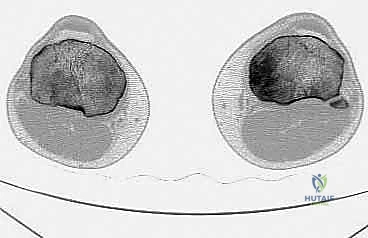

لفهم مدى تعقيد وعبقرية جراحة استئصال الظنبوب القريب، من الضروري الإبحار في أعماق التشريح الأساسي لهذه المنطقة الحيوية. لا يقتصر الأمر على مجرد عظام، بل هو نظام هندسي وبيولوجي متكامل ومعقد. يتكون مفصل الركبة من التقاء عظم الفخذ (Femur) من الأعلى، وعظم الساق أو الظنبوب (Tibia) من الأسفل، وعظم الشظية (Fibula) الجانبي، بالإضافة إلى الرضفة أو صابونة الركبة (Patella) في الأمام. الجزء القريب من الظنبوب هو الجزء العلوي العريض من عظم الساق، والذي يشكل القاعدة الأساسية التي يستند عليها مفصل الركبة ويتحمل وزن الجسم بأكمله.

* الساركوما العظمية (Osteosarcoma): وهو النوع الأكثر شيوعاً، ينشأ في الخلايا المكونة للعظم، ويتميز بنموه السريع والعدواني وتدميره للعظم المحيط.

* ورم الخلايا العملاقة (Giant Cell Tumor - GCT): هو المثال الأبرز في هذه الفئة. ينشأ غالباً في نهايات العظام الطويلة بالقرب من المفصل (مثل الظنبوب القريب). في الحالات المتقدمة التي يدمر فيها الورم القشرة العظمية وسطح المفصل، يصبح الاستئصال الكامل وإعادة البناء بالطرف الصناعي هو الخيار الأمثل لمنع عودة الورم (Recurrence).